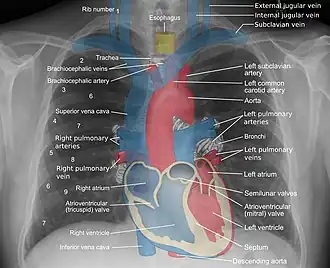

Landmarks

A chest radiograph with the angle parts of the ribs and some other landmarks labeled.

Mediastinal structures on a chest radiograph.

In the average person, the diaphragm should be intersected by the 5th to 7th anterior ribs at the mid-clavicular line, and 9 to 10 posterior ribs should be viewable on a normal PA inspiratory film. An increase in the number of viewable ribs implies hyperinflation, as can occur, for example, with obstructive lung disease or foreign body aspiration. A decrease implies hypoventilation, as can occur with restrictive lung disease, pleural effusions or atelectasis. Underexpansion can also cause interstitial markings due to parenchymal crowding, which can mimic the appearance of interstitial lung disease. Enlargement of the right descending pulmonary artery can indirectly reflect changes of pulmonary hypertension, with a size greater than 16 mm abnormal in men and 15 mm in women.[6]

Appropriate penetration of the film can be assessed by faint visualization of the thoracic spines and lung markings behind the heart. The right diaphragm is usually higher than the left, with the liver being situated beneath it in the abdomen. The minor fissure can sometimes be seen on the right as a thin horizontal line at the level of the fifth or sixth rib. Splaying of the carina can also suggest a tumor or process in the middle mediastinum or enlargement of the left atrium, with a normal angle of approximately 60 degrees. The right paratracheal stripe is also important to assess, as it can reflect a process in the posterior mediastinum, in particular the spine or paraspinal soft tissues; normally it should measure 3 mm or less. The left paratracheal stripe is more variable and only seen in 25% of normal patients on posteroanterior views.[7]

Localization of lesions or inflammatory and infectious processes can be difficult to discern on chest radiograph, but can be inferred by silhouetting and the hilum overlay sign with adjacent structures. If either hemidiaphragm is blurred, for example, this suggests the lesion to be from the corresponding lower lobe. If the right heart border is blurred, than the pathology is likely in the right middle lobe, though a cavum deformity can also blur the right heard border due to indentation of the adjacent sternum. If the left heart border is blurred, this implies a process at the lingula.[8]